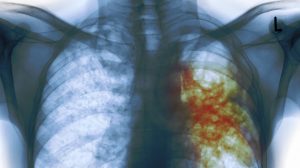

وإذا كان لدى الشخص المصاب فحص إيجابي لكل من الجلد أو الدم، فمن المحتمل أن يطلب منه الطبيب أشعة سينية على الصدر أو الأشعة المقطعية للبحث عن أي تغيرات في الرئة وقد يقوم الطبيب أيضًا باختبار بكتيريا الدرن في البلغم وهو المخاط الذي يظهر عند السعال.